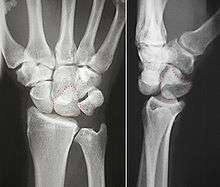

![]() Left hand anterior view (palmar view). Lunate bone shown in red. | |

The lunate bone (semilunar bone) is a carpal bone in the human hand. It is distinguished by its deep concavity and crescentic outline. It is situated in the center of the proximal row carpal bones, which lie between the ulna and radius and the hand. The lunate carpal bone is situated between the lateral scaphoid bone and medial triquetral bone.

The lunate is a crescent-shaped carpal bone found within the hand. The lunate is found within the proximal row of carpal bones. Proximally, it abuts the radius. Laterally, it articulates with the scaphoid, medially with the triquetral, and distally with the capitate. The lunate also articulates on its distal and medial surface with the hamate bone.[1]:708[2]

The proximal surface of the lunate bone is smooth and convex, articulating with the radius. The lateral surface is flat and narrow, with a crescentic facet for articulation with the scaphoid. The medial surface possesses a smooth and quadrilateral facet for articulation with the triquetral. The palmar surface is rough, as is the dorsal surface. The dorsal surface is broad and rounded. The distal surface of the bone is deep and concave.[3]

The lunate bone is the most frequently dislocated carpal bone.